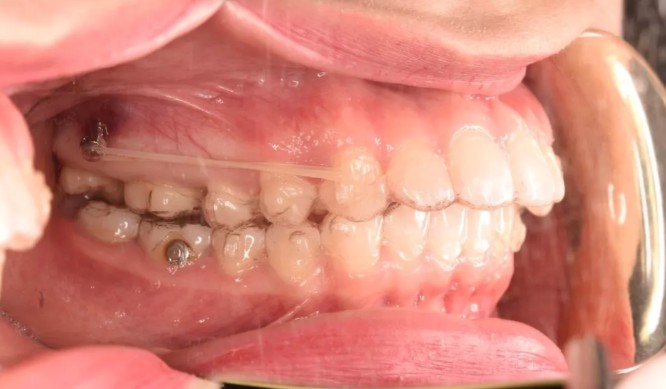

溫州鹿城牙博士開設(shè)有口腔種植、牙齒矯正、牙齒修復(fù)、牙齒美白、牙周治療、兒童齒科等六大科室,其中數(shù)字化美學(xué)矯正、微創(chuàng)即刻種植牙、All-on-4種植牙是院內(nèi)的特色項(xiàng)目。

牙博士口腔會(huì)根據(jù)顧客的臉型進(jìn)行數(shù)字化設(shè)計(jì),準(zhǔn)確矯正(不拔牙或少拔牙),同時(shí)還能縮短矯正的時(shí)間,讓顧客更快的享受到治療后的結(jié)果。